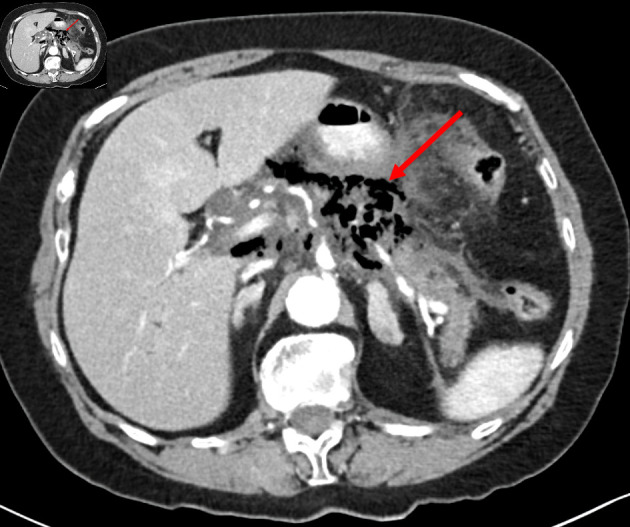

气肿性胰腺炎(EP)是一种严重的胰腺坏死性感染,是一种极为罕见的急症,死亡率很高。其特点是胰腺实质内或胰腺周围充气,原因是单微生物或多微生物感染产气细菌,或者是肠胰瘘。急性胰腺炎根据计算机断层扫描(CT)发现气泡征象的起病时间分为早期起病(起病两周内)和晚期起病(起病两周以上)。虽然大多数急性胰腺炎病例仅通过支持性治疗即可缓解,但 EP(尤其是早发亚型)的临床预后非常差,发病率和死亡率都很高。这两份病例报告介绍了我院收治的两名早发暴发性急性胰腺炎患者的临床特征、诊断检查和治疗情况,他们分别接受了不同的检查和治疗。第一例患者接受了更为保守的治疗,在入院 52 小时后才确诊,因此推迟了入住重症监护室(ICU)和手术的时间;而第二例患者在发病数小时后才确诊,并提前入住重症监护室。在本文中,我们将介绍早期诊断上述罕见重症胰腺炎的重要性,并探讨快速诊断对病程、发病率和死亡率的影响。

Emphysematous pancreatitis (EP), a severe form of necrotizing infection of the pancreas, is an extremely rare medical emergency with high rates of mortality. It is characterized by intraparenchymal pancreatic or peri-pancreatic air due to either monomicrobial or polymicrobial infection with gas-forming bacteria or due to entero-pancreatic fistula. EP is classified according to timing from disease onset when air bubble signs were detected on computed tomography (CT) scan, as early onset (within 2 weeks from disease onset) or late (more than 2 weeks from disease onset). While most cases of acute pancreatitis are resolved with supportive care alone, clinical outcomes of EP, especially the early onset subtype, are very poor with high rates of morbidity and mortality. These two case reports present the clinical features, diagnostic investigations, and management of two patients admitted to our hospital with early onset fulminant EP, each investigated and managed with different approaches. The first patient underwent a more conservative treatment, with diagnosis being made 52 h following admission, and thus, intensive care unit (ICU) admission and surgery were postponed, while the second patient was diagnosed a few hours following presentation with earlier ICU admission. In this article, we will present the critical importance of early diagnosis of the aforementioned rare entity of severe pancreatitis and will consider the consequences of rapid diagnosis on disease course, morbidity and mortality.